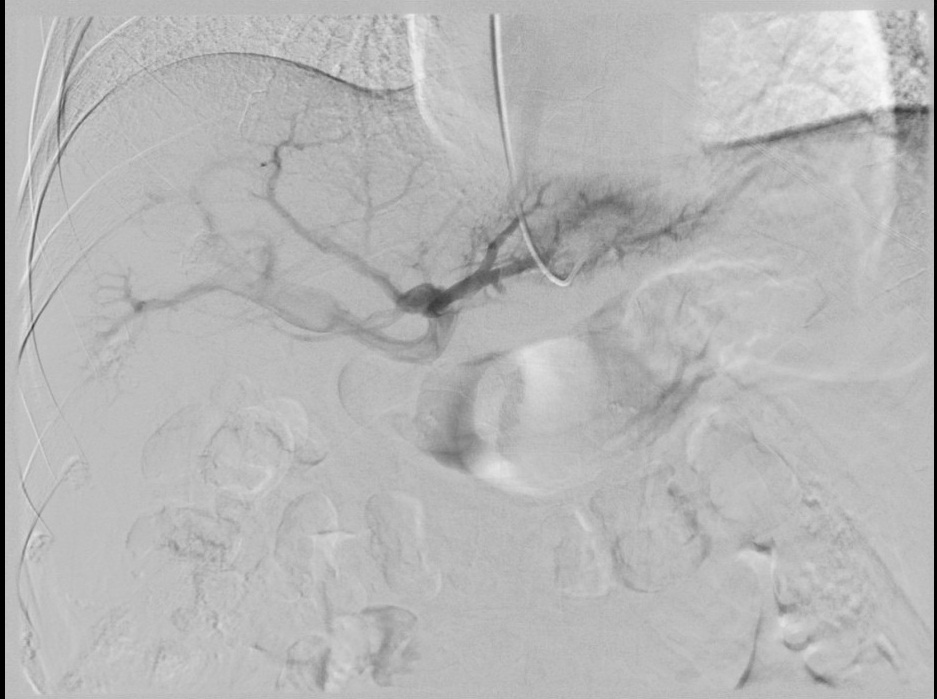

门静脉海绵样变是指肝门部或肝内门静脉分支慢性、部分性或完全性阻塞后,导致门静脉血流受阻,引起门静脉压力增高,同时在门静脉周围形成侧支循环。针对该病,中国工程院院士、北京清华长庚医院执行院长董家鸿开展的Meso-Rex术为目前最前沿的外科治愈性技术,术前精确肝内门静脉评估是手术治疗的前提。传统的方式是直接经皮经肝穿刺行门静脉造影术,失败率较高,对肝脏有一定损伤,容易出现腹腔出血、包膜下出血、胆漏、肝动脉假性动脉瘤等相关并发症。张琳副主任医师和黄鑫医师联手,在国内率先开展了经肝静脉楔入门静脉造影术,利用肝小叶内肝静脉与门静脉互通的原理,实现完整显示肝内门静脉分支及走行,为实施Meso-Rex术提供充分依据。张琳表示,肝胆介入科医师实施经肝静脉楔入门静脉造影术,需全面了解肝静脉结构、走行,门静脉病变范围、特点,关键在于选择恰当的楔入肝静脉分支及部位。

门静脉海绵样变患者经肝静脉楔入门静脉造影,门静脉分支显示良好